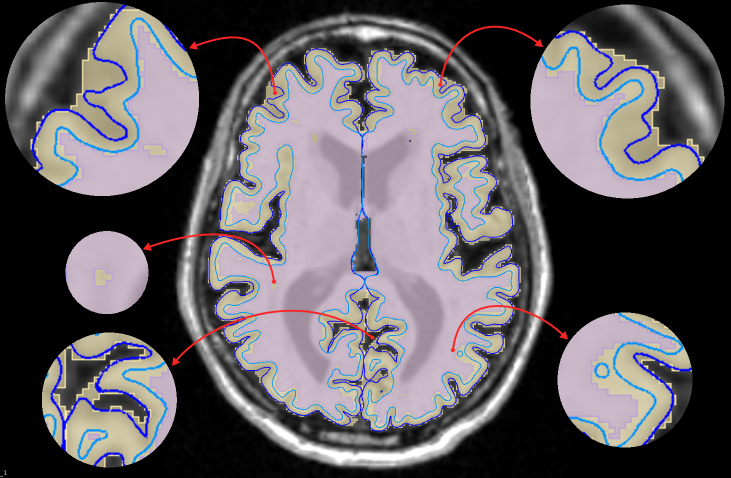

CorticalFlow also generates triangular meshes with better properties than the evaluated methods. Compared to the deformation-based methods NMF and Voxel2Mesh, CorticalFlow predicted meshes are genus-zero surfaces and present a lower percentage of self-intersecting faces (mainly for the inner cortical surfaces). Figure 5(a) presents examples of self-intersecting faces produced by CorticalFlow, which are contrasted with the NMF predicted mesh for the same input MRI. The implicit-surface-based DeepCSR method does not produce a single self-intersecting face since it employs computationally expensive post-processing routines like topology correction [4] and iso-surface extraction. However, these post-processing routines do not take into account the input MRI which can generate non-plausible corrections on the output mesh as previously observed in Segonne et al. [67] and exemplified in Figure 5(b). Similarly, the voxel-wise segmentation baseline (i.e., QuickNAT) is free of self-intersecting faces, but it does not produce genus-zero surfaces. Indeed, QuickNAT’s predicted surfaces are composed of multiple connected components presenting many handles and holes which is not acceptable for the purpose of cortical surface reconstruction. Some examples of QuickNAT reconstructed cortical surfaces are presented in our supplementary material. Therefore, we argue that CorticalFlow is the method of choice to reconstruct regular surfaces from volumetric images.

Finally, as a by-product of CorticalFlow’s deformable and diffeomorphic nature, one can seamlessly obtain a sub-voxel resolution segmentation by applying a voxelization engine. This can capture variations below the image resolution while traditional segmentation methods [64] are restrained from working at the image resolution (see Figure 6(a)). Additionally, an essential component of computational neuro-anatomy consists of computing local shape descriptors for different individuals and transferring them to the same reference space using conformal mappings [29, 70]. For the proposed model, one can efficiently compute the inverse transformation as shown in Figure 6(b) for the surface curvature descriptor.